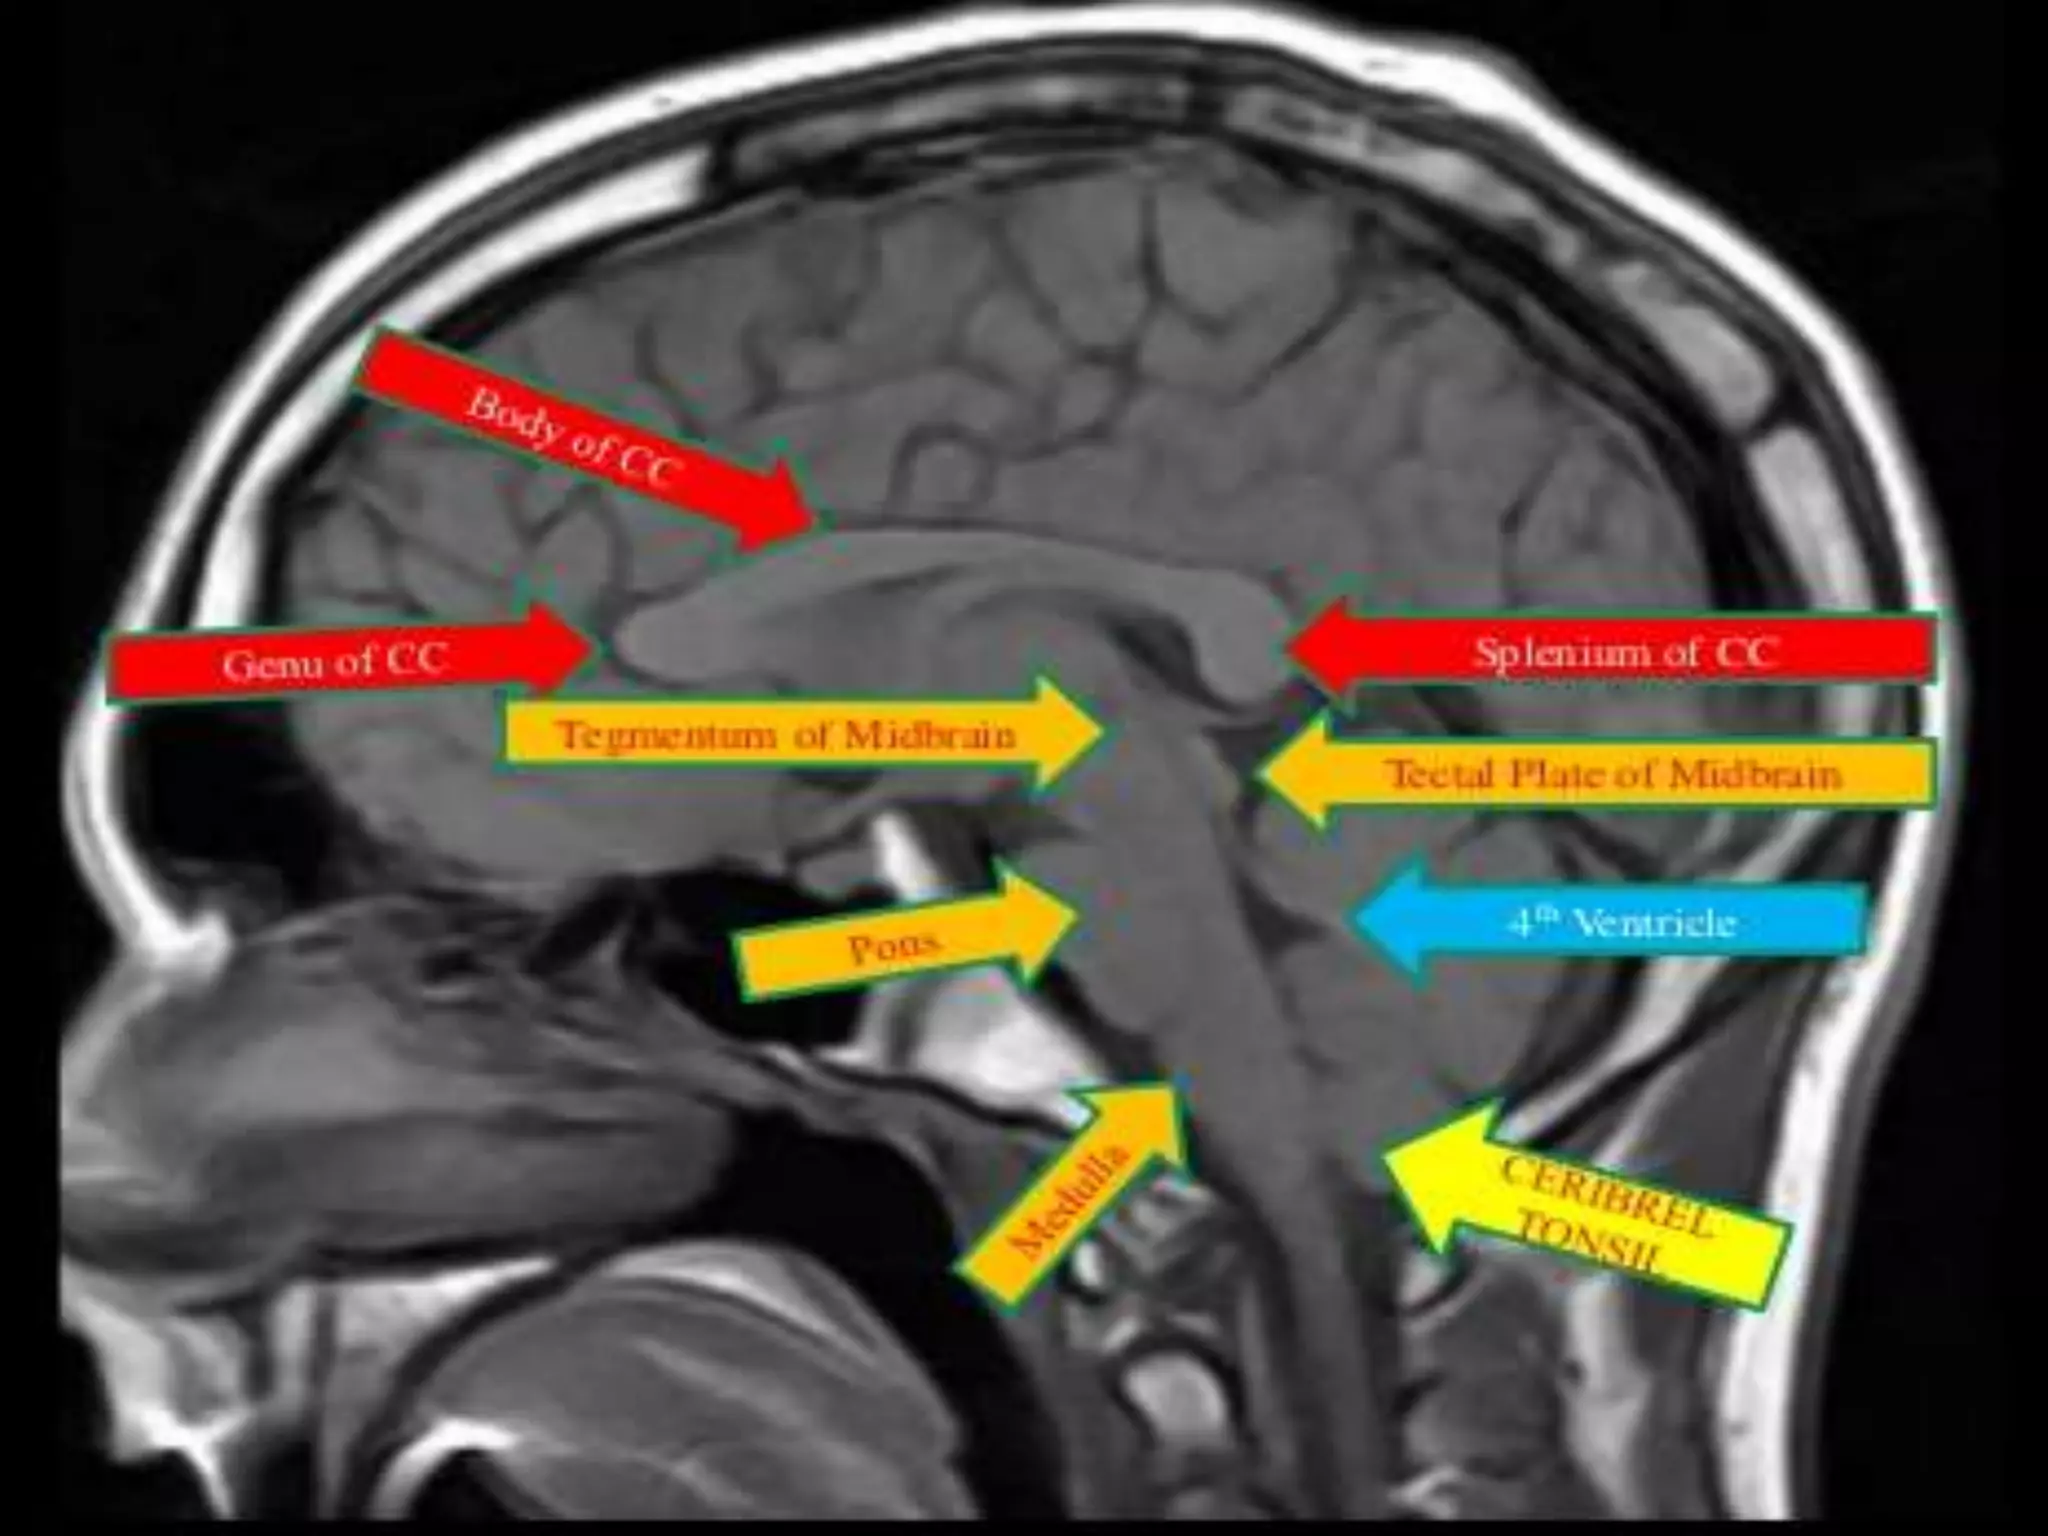

Sectional Anatomy: NormalAxial CT and MRI Anatomy. On CT and MR scans, the brain has been briefly viewed in infratentorial and supratentorial sections, as described below. CT scans are performed with a 15- to 20-degree angulation to the canthomeatal line at 8-mm increments. MRI scans are generally obtained parallel to the AC-PC line in the axial plane with 6-mm slice thickness. Using the sagittal view, the coronal sections are acquired parallel to the brain stem, and the sagittal sections are obtained perpendicular to the axial section. On MRI studies, cranial nerves IX and X can be demonstrated at this level because they emerge from the postolivary sulcus. The posterior aspect of the cerebellar hemispheres is outlined by the inferior portion of the cisterna magna.